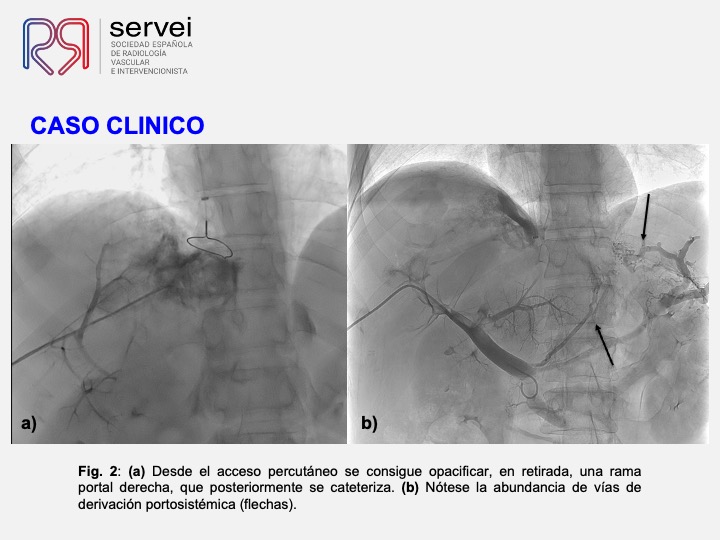

DIPS con técnica de “gun-sight”. Paciente con Síndrome de Budd-Chiari y eventual trombosis protésica